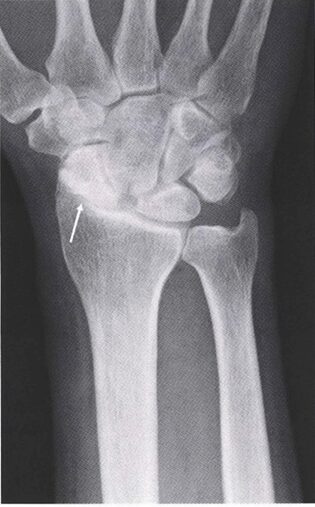

図3.SLAC wrist

SL間は解離し、橈骨舟状関節は著明な狭小化を認める(矢印)

出典:中村 俊康 “手根骨間靱帯損傷, 手根不安定症とその治療.” *MB Orthopaedics* 32, no. 4 (2019): 79-84.